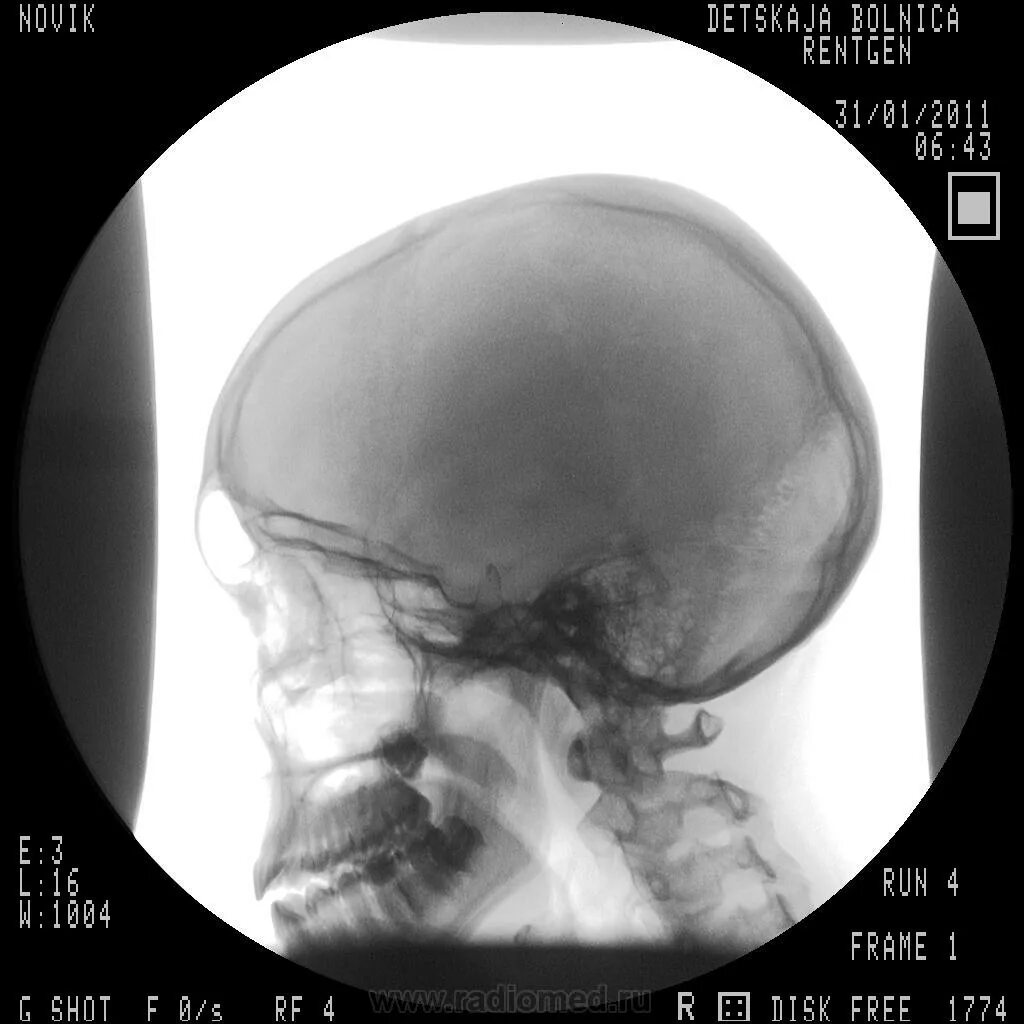

Спинка турецкого седла